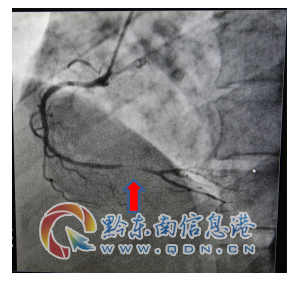

該患者入院查肌鈣蛋白、心肌酶增高,復(fù)查心電圖提示“Q波加深、ST段下移較前明顯”,結(jié)合輔助檢查結(jié)果陳文海主任對(duì)患者病情診斷為急性心肌梗死,考慮患者合并有糖尿病、甲亢等多種病癥,病情緊急,需按照胸痛中心急性心肌梗死流程緊急處理。經(jīng)過(guò)該院心血管內(nèi)科專(zhuān)家的會(huì)診評(píng)估,認(rèn)為及早行冠脈介入診療對(duì)患者是有益的。征得該患者及家屬的同意后,立即啟動(dòng)導(dǎo)管室行冠脈造影檢查,造影提示右冠脈遠(yuǎn)段重度狹窄病變,在李健民副主任醫(yī)師的指導(dǎo)下,心血管內(nèi)科陳文海主任、楊文林醫(yī)師對(duì)患者繼續(xù)行藥物球囊擴(kuò)張術(shù),選擇支架植入為補(bǔ)救治療方案。冠脈介入過(guò)程謹(jǐn)慎細(xì)致,最后判斷冠脈藥物球囊擴(kuò)張術(shù)對(duì)患者獲益更大后,予以藥物球囊擴(kuò)張術(shù),不需植入冠脈支架,造影復(fù)查嚴(yán)重狹窄病變處經(jīng)藥物球囊擴(kuò)張術(shù)處理后,殘余狹窄小于30%,達(dá)到治療效果。手術(shù)過(guò)程歷經(jīng)不足半小時(shí),成功開(kāi)通狹窄病變的冠脈血管,TIMI血流3級(jí),手術(shù)效果滿意,術(shù)后患者安返病房,未再出現(xiàn)胸痛癥狀。

術(shù)前病變(箭頭所示)